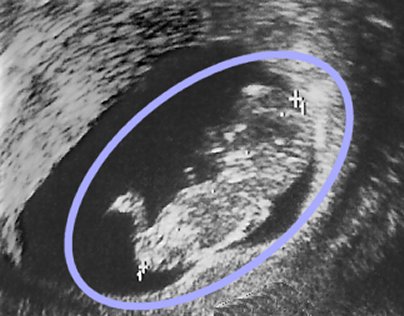

Exemplo de Sonograma

Este sonograma, tirada no 3º mês de gravidez, mostra um feto masculino (cabeça, corpo e pernas estão bem reconhecíveis dentro do circulo azul oval).